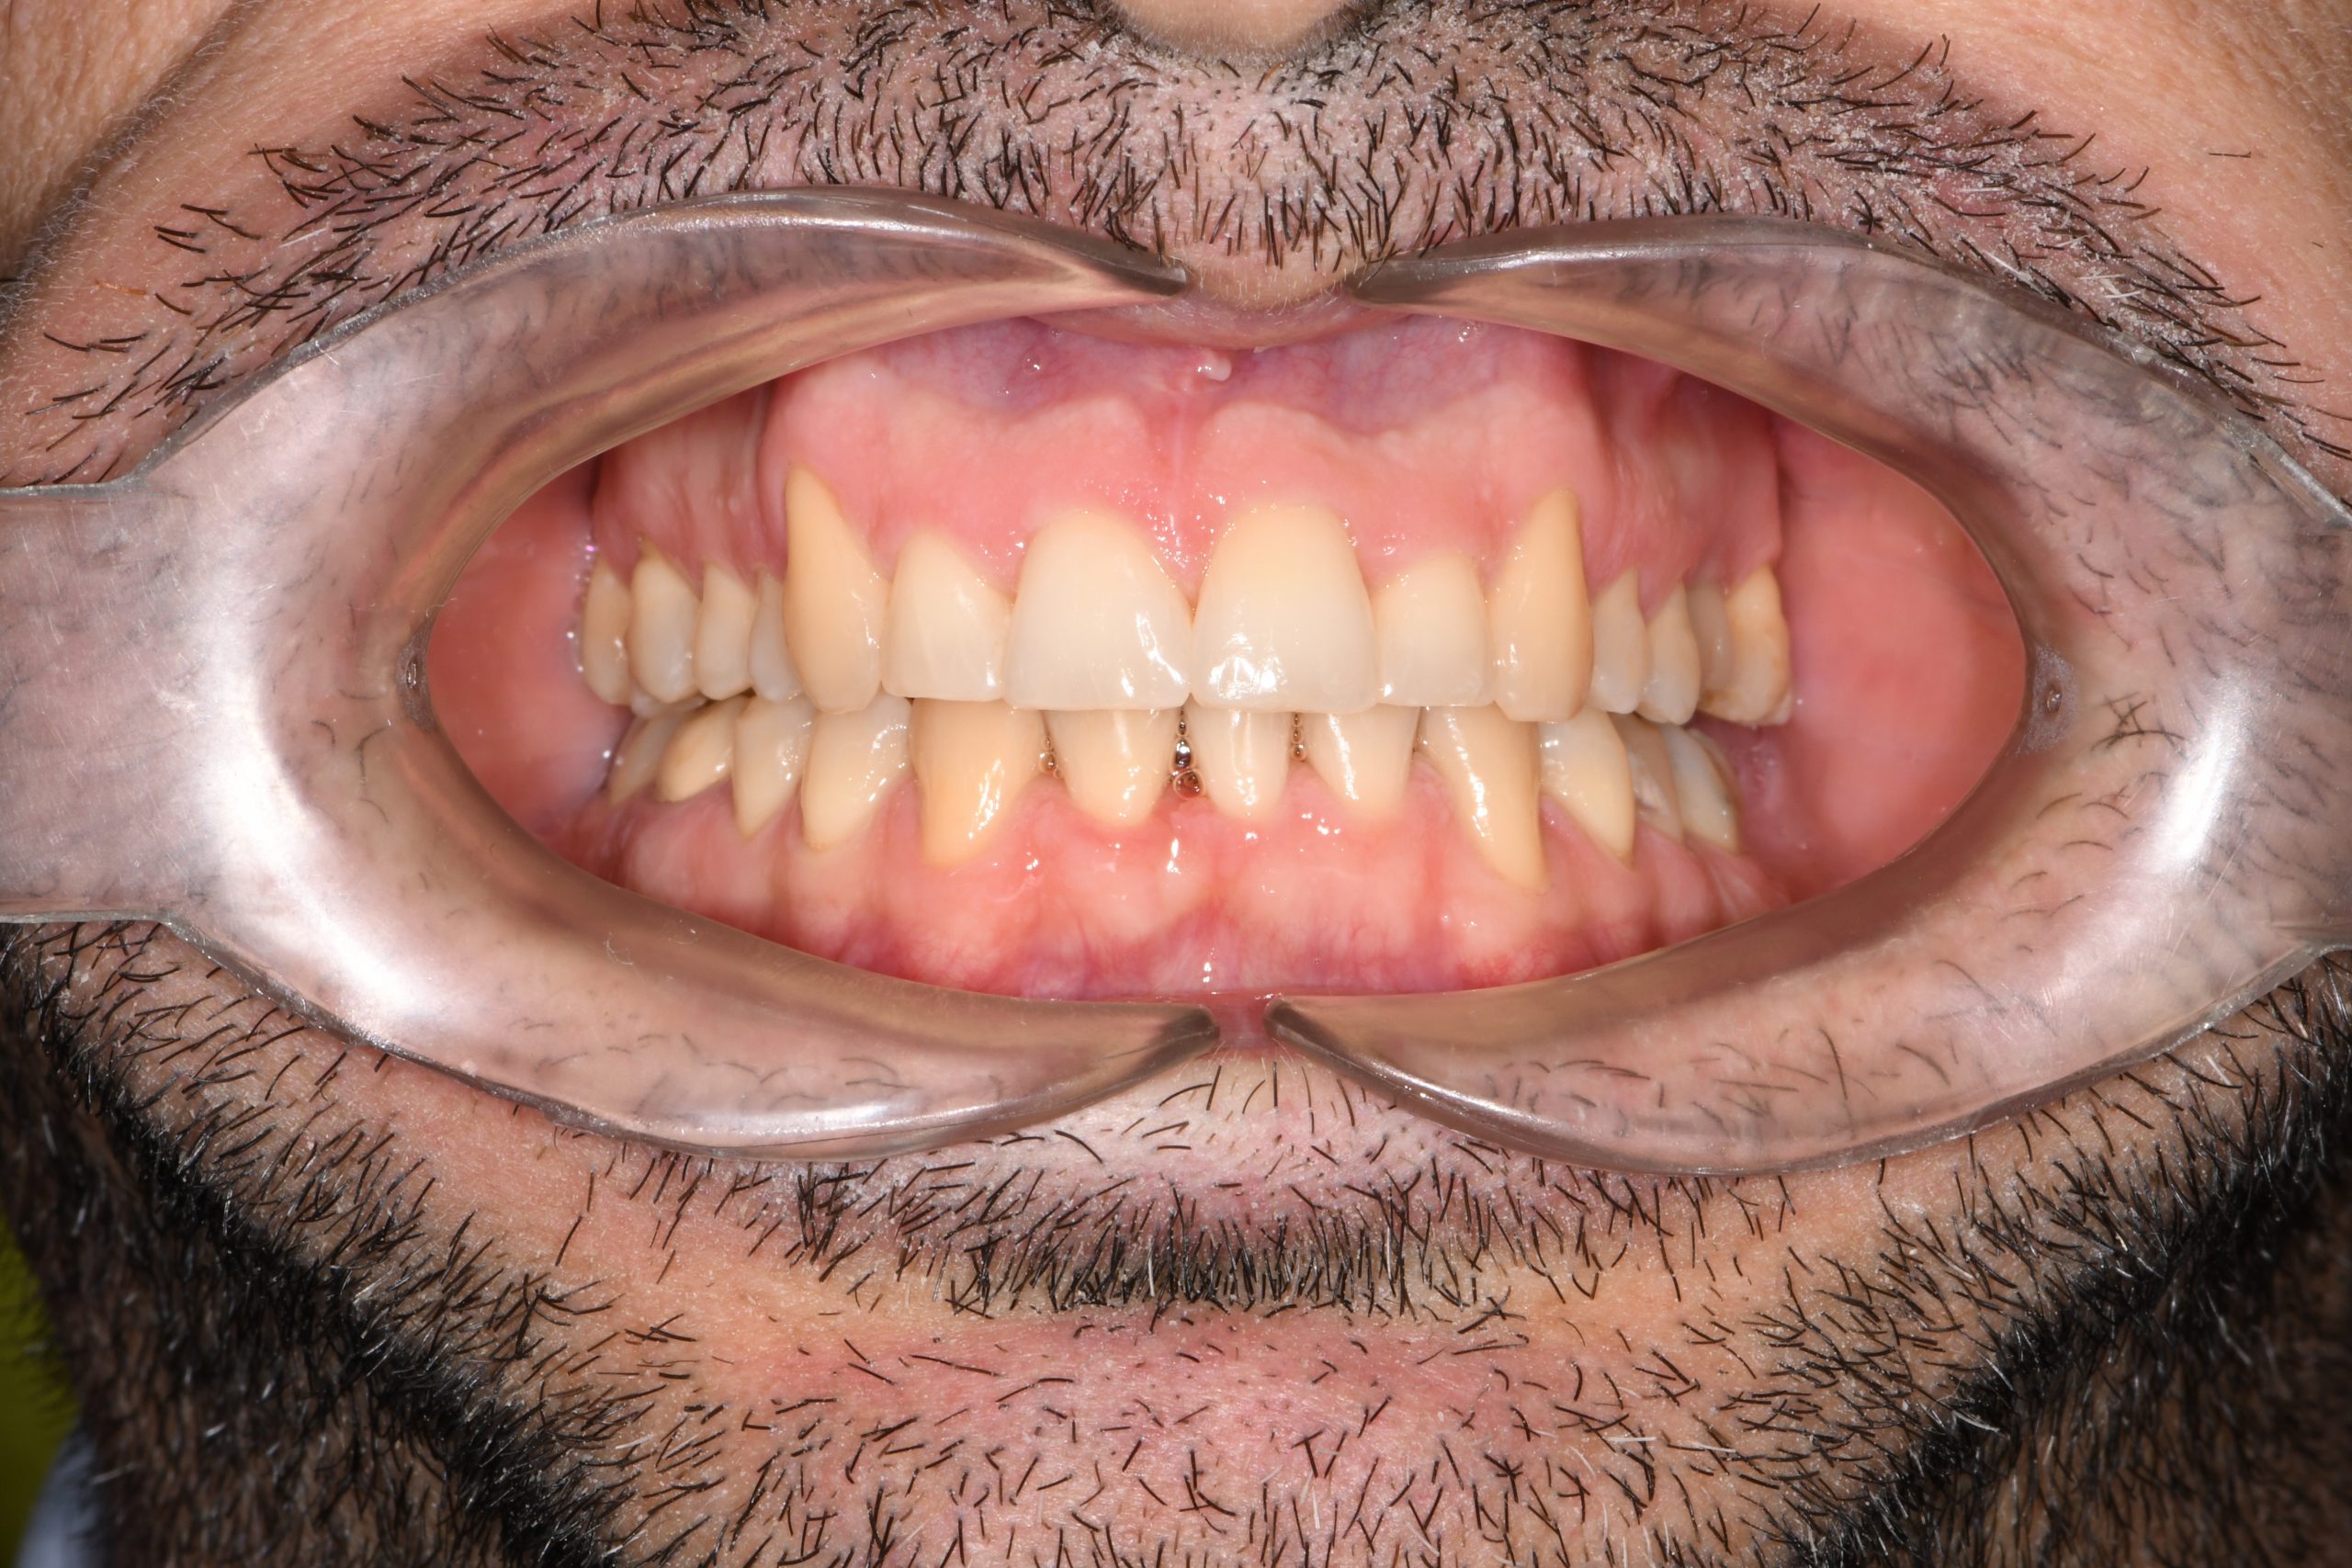

Az elmúlt évekből rengeteg szakmai referenciát tudnánk bemutatni, amelyek különböző fogszabályozási problémákat oldottak meg. Válogatva a több száz esetből, ezen az oldalon olyan képeket, információkat igyekeztünk bemutatni, amelyeknek a segítségével a jövőbeni pácienseinknek azt tudjuk üzenni: A Te fogsorod is lehet gyönyörű!

(Képeket a Pácienseink külön írásos beleegyezésével mutatjuk be!)